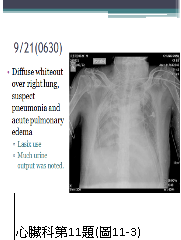

11. 病人82歲男性,主訴有寒顫(chills)及漸進性呼吸困難的兩天病程,同時伴有咖啡色嘔吐物。他有高血壓、左迴旋枝支架置放之冠心病及腦中風而左半邊麻痺的多年病史。血壓 125/64;心跳 100/min;體溫 38.6度;呼吸 24/min;心尖部有Gr 4/6 systolic murmur;肺部有濕性濁音,雙腳水腫;其他尚無重大異常。實驗室:WBC 9610/mm3,segment neutrophils 88%;Hb 10.0 g/dL;C-Reactive protein 1.69 ng/mL;CK 221 ng/mL; CK-MB 16 U/L;Troponin I 1.36 μg/L;尿檢有蛋自尿(++),大便潛血,(++);其心電圖及胸部X光如圖11-1及圖11-2所示。三、八及十二小時後之CK及CK-MB,分別為1340、1462、1422及40、44、38。且在翌日追蹤胸部X光如圖11-3所示。隨即 (1).逕行血液及痰細菌培養及啟用Unasyn 1g q8h及azithromycin 500 mg qd (2)輸2u packed cell RBC (3).靜脈注射Furosemide 20 mg (4)使用Clopidogrel 150 mg & then 75 mg qd 及Aspirin 80 mg qd (5)Heparin25,000 u/day (6)會診心臟科 請問下列哪一組的處置較恰當? (A) (1)+(2)+(5) (B) (1)+(3)+(6) (C) (1)+(4)+(6) (D) (2)+(5)+(6) (E) (3+(4)+(5)